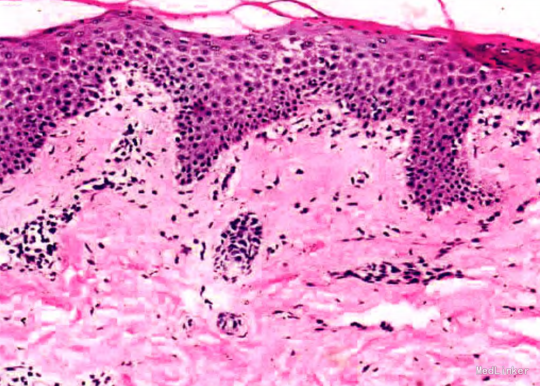

体格检查:生命体征平稳,系统查体未见明显异常。皮肤科检查:躯干及四肢泛发大量粟米至绿豆大红色斑、丘疹,界清,表面覆少许细小鳞屑,点状出血现象阴性。皮损组织病理检查:表皮轻度角化过度伴灶性角化不全,棘层局部海绵形成;真皮浅层血管周围少许慢性炎性细胞浸润。实验室及辅助检查:血、尿常规,肝、肾功能,总免疫球蛋白(Ig)E均无明显异常.梅毒特异性抗体、梅毒反应素试验阴性。